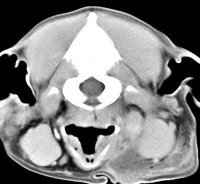

imágenes de TC en el perro | ||||||||||

ejemplo de imágenes de TC en el perro. Nótese la celulitis en la región parotídea izquierda | ||||||||||